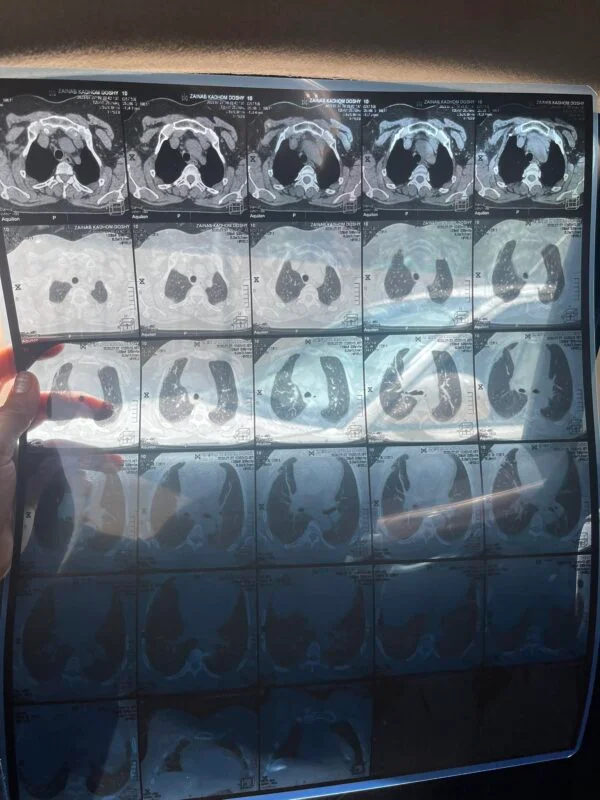

الحالة الإنسانية (8): امرأة تحتاج علاج لسرطان الثدي

أنا مريضة بسرطان الثدي، أعاني من صراع صحي صعب، وأجد نفسي في موقف مالي صعب حيث ليس لدي المبلغ اللازم للعلاج والرعاية اللازمة، وزوجي مريض وعاطل عن العمل، وليس لنا معيل.

ثانيا: كانت هذه المرأة تأخذ علاجات بشكل متقطع لضيق اليد، ثم توقفت نهائيا عن اخذ العلاج.

ثالثا: تبين انها تحتاج شهريا قرابة (200$) للعلاج فضلا عن رسوم الفحوصات الدورية.

تم اخذ المريضة الى الطبيب المختص واخبرنا ان هناك ورم بسيط في الثدي الاخر وان شاء الله يمكن ان يختفي بالعلاج لكن يجب ان تستمر على العلاج دون انقطاع نهائيا لضمان عدم رجوع المرض او انتشاره في اماكن اخرى. وبحمد الله وفضله تم تأمين وتسليم المريضة الدواء الذي تحتاجه لمدة شهر.